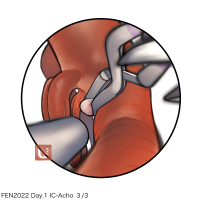

FEN2022シリーズ